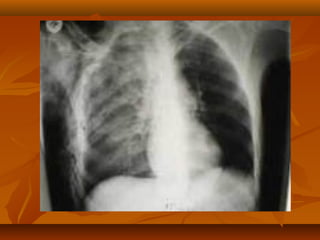

HEMATOTHORAX

Penimbunan darah dalam cavum

pleura.

Berasal dari Paru

:a.intercostalis,a.mammaria

interna,mediastinum,jantung,

organ abdomen.

Terapi.

1.konservatif.

2.WSD.

monitoring :-0-3 cc/kg BB/jam

 observasi.

3-5 cc/kg BB/jam  observasi

ketat.

>5 cc/kg BB/jam  torakotomi